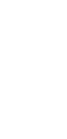

Thymic carcinoid tumours, especially in the context of multiple endocrine neoplasia type 1 (MEN 1), present significant clinical challenges due to their rarity and aggressive nature. This case report describes a complex patient with MEN 1, who suffered from multiple manifestations of the disease, including thymic carcinoid. The tumour was initially resected and treated with adjuvant radiotherapy. Due to slow progression over the years, the tumour was treated with two lines of chemotherapy before the patient succumbed to progressive disease. There is currently limited evidence favoring any specific medical treatment for thymic carcinoid.